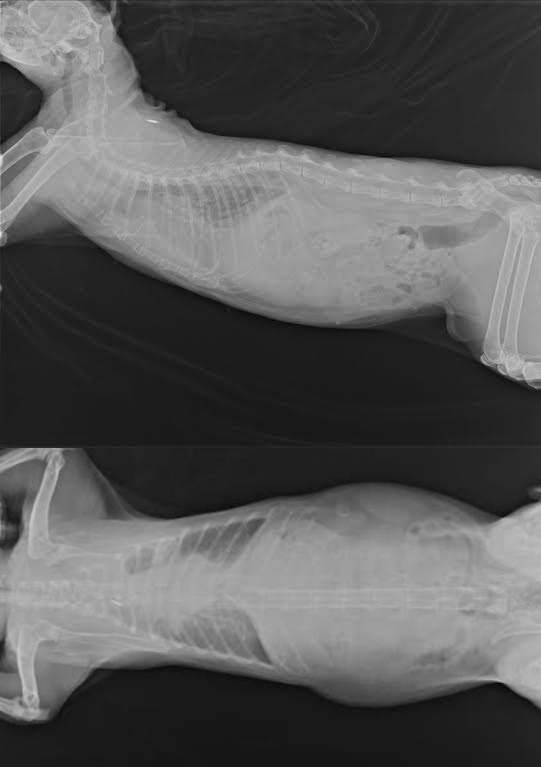

- 編號: 4824

主題: 麵包超人癌症擴散 申請者姓名: 臺北市支持流浪貓絕育計劃協會 花色: 申請日期: 2014-08-13 21:54:42 申請者部落格: 申請者臉書網址: 所在縣市/合作醫院: 台北市/極光動物醫院 治療費用: 8055元 需求人數: 18人 已結案 (2014-09-04 10:06:02) 報名人員: yu-j(已付款)、Yahui Chung(已付款)、lunacyryu x2(已付款)、盧(已付款)、meme(已付款)、Sunny Chen(已付款)、尤品侖(已付款)、陳曉霏(已付款)、Irena x2(已付款)、Moonin(已付款)、貓尾巴(已付款)、romeart(已付款)、romeart(已付款)、Summer(已付款)、Mimi Chen(已付款)、Wen-ling Tsai(已付款)、 候補人員: 動物病情說明: 7/25 麵包超人最後一次回診化療,X光追蹤癌細胞擴散到胸腔了,並且產生胸水,血檢指數正常,按計畫進行化療,希望可以為麵麵爭取多一點時間享福,抽了40CC胸水,之後每周需固定回診確認胸水情況,也會特別留意他的呼吸狀況,目前雖然有胸水但呼吸狀況仍很穩定,口服藥 : 1天2次,一周後回診,依然有胸水產生,尚未影響精神食慾,每天加量的高級罐罐和精美的零食小餅乾,麵麵總是開心的大吃大喝,過著老佛爺般的生活,有ㄧ堆貓奴才伺候。